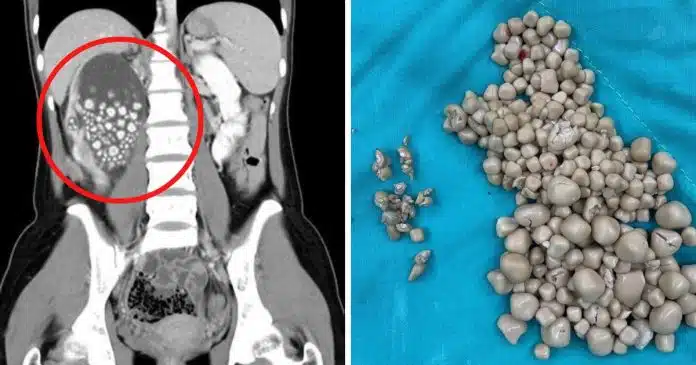

Os médicos administraram-lhe antibióticos e realizaram um procedimento minimamente invasivo para remover as centenas de pedras nos rins acumuladas, que tinham uma aparência semelhante a “pãezinhos cozidos no vapor”, segundo os médicos.

Mais de 300 cálculos renais foram removidos da paciente, medindo entre 0,5 cm e 2 cm de diâmetro.